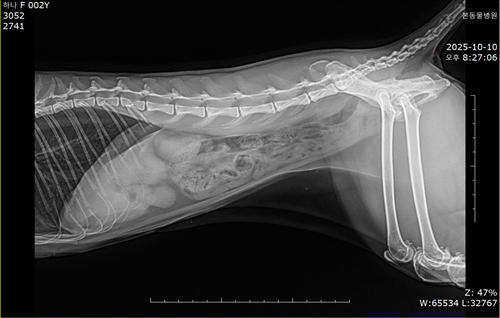

10.10/10.12/10.14일 엑스레이입니다

10월 10일 포도를 토해논후로 식욕저하 기력저하가 있어서 동물병원에 방문해서 엑스레이를 찍었는데 우선 지켜보자는 말과 소화제처방과 주사를 맞고 집왔습니다 그 후로도 안먹어서 12일에 동물병원에가서 혈액검사도 하고 수액도 맞았습니다 췌장쪽 수치가 좀 높아서 췌장쪽만 다시 검사했는데 수치는 괜찮았습니다 식욕촉진이랑 소화제처방 받아서 먹이는데 식욕저하도 여전하고 기력이 좀 없고 10일부터 14일까지 대변을 못보고있어서 14일에 병원에 가서 엑스레이랑 초음파를 했는데 장폐색일수도 있다는 말을 들었습니다 초음파상으로는 소장쪽 이물이 의심된다고 하셨어요ㅠ

우선은 그냥 집에 데려왔는데 집에오니까 밥도 조금씩 자주 잘먹고 드디어 오늘 아침에는 대변을 봤습니다 구토는 10일에 한번만 하고 아직까지 구토증상 없어요ㅠ 그리고 밥도조금씩 자주 먹더라구요ㅠ 원래가 먹는양이 많은 애는 아니었는데 예전에 비하면 먹는 횟수가 많아지고 한번 먹을때 양은 좀 작아지긴했어요ㅠ 장폐색으로 보이는지 여쭤보고싶어서 문의드립니다ㅠㅠ 저 혈액검사는 12일에 한거입니다 오늘 아침에 본 대변도 추가합니다ㅠㅠ 잘좀 봐주세요ㅠㅠ